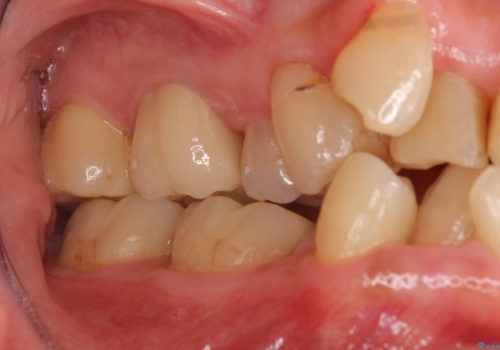

奥歯の銀歯、プラスチックのやりかえ

- 奥歯の詰め物のやり替えを希望して来院。

銀歯と、プラスチックをセラミックにかえました。

古い詰め物を取るときに、しっかり虫歯はとっています。

右上6番は詰め物が大きく、インレーではなくクラウンとしました。